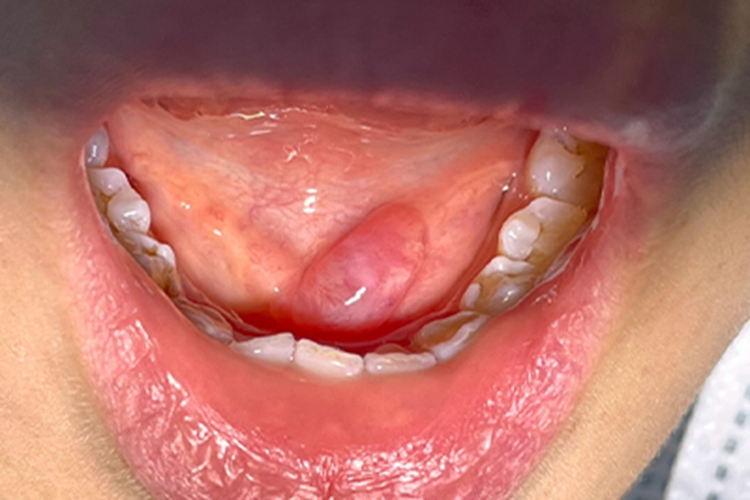

涎腺囊肿可出现口腔软包样损害,初期可发现导管囊性扩张,继之形成囊肿,触之柔软。与周围界限清晰,没有疼痛感。若有感染时可合并疼痛及压痛。

涎腺囊肿可发生在腮腺、颌下腺及舌下腺区,涎腺导管因炎症或结石阻塞使腺体分泌物潴留所致,阻塞原因多系损伤,有时多次反复损伤,可形成瘢痕而阻塞排泄管。